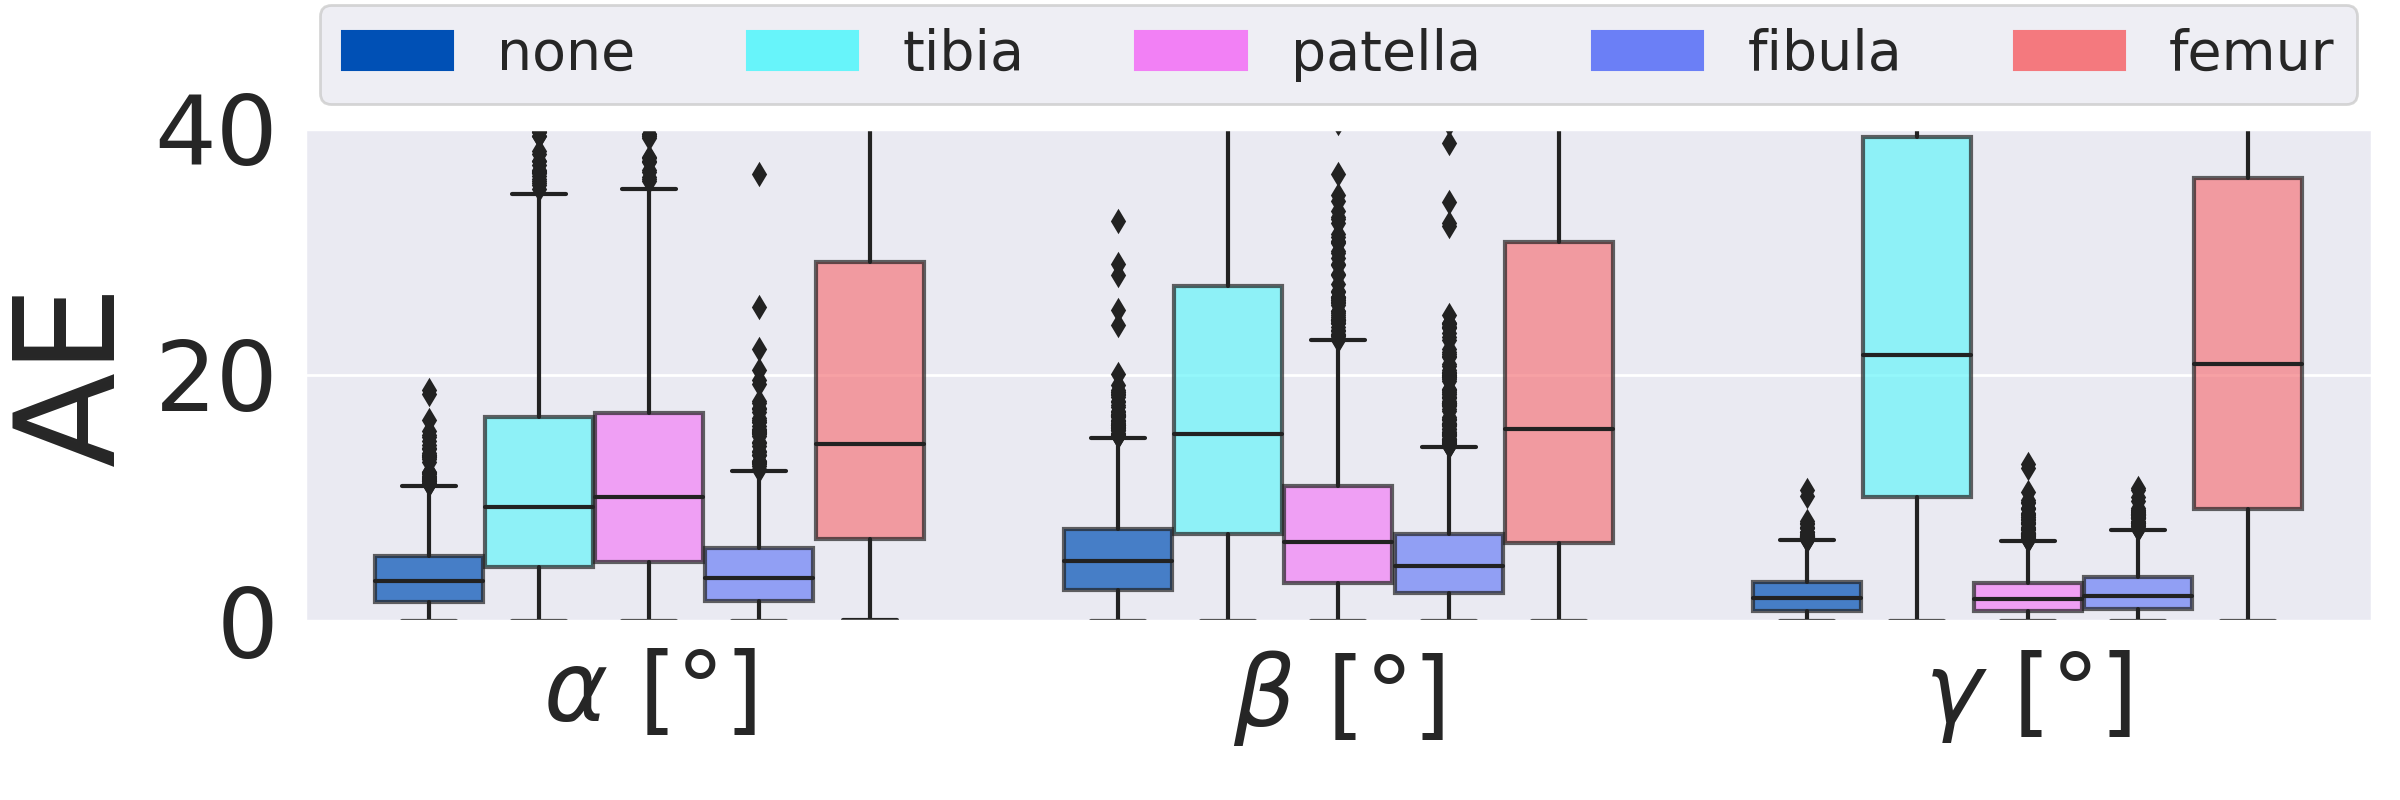

3.2 Importance of individual bones on overall performance (RQ2)

Fig. 7 shows the importance of individual segmented bone classes on the overall positioning performance evaluated on the test DRRs (3528 DRRs). The fibula has very little influence on the positioning for both views. The patella is only important for the a.-p. view, while tibia and femur are relevant for both views. The condyle assignment for the lateral view determines the rotation direction for the orbital and angular rotation (, ). Inverting the assignment of left and right femur condyle results in a sign flip in , .